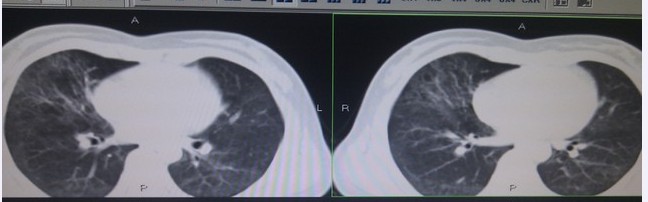

肺部磨玻璃密度影(ground glass opacity,GGO)是指高分辨率CT图像上表现为密度轻度增加的一类非特异性影像学表现,但支气管血管纹理仍可显示,常见于肺部出血、炎症、肿瘤和纤维化等病变。目前研究结果显示,GGO最常见的原因是肺癌,其次是炎症、血管炎,腺瘤样增生。肺癌中主要是肺泡细胞癌,其次是腺癌。GGO是临床诊断难点,必须综合临床表现及其他检查结果一起分析,方能避免误诊。根据范围可分为弥漫性和局灶性两种。

肺部密度主要由肺内气体、体液、血液、肺组织本身密度构成,肺部疾病导致上述因素改变时可间接导致肺部密度改变,肺部磨玻璃影显示肺部密度改变的一种非特异性征象,在肺部多种疾病中均可出现,其中局限性肺磨玻璃影与周围肺组织对比明显,容易诊断,但是弥漫性肺磨玻璃影难以确定, 因此各部位肺部疾病磨玻璃影分布特点伴随症状对明确诊断方向有一定的促进意义。